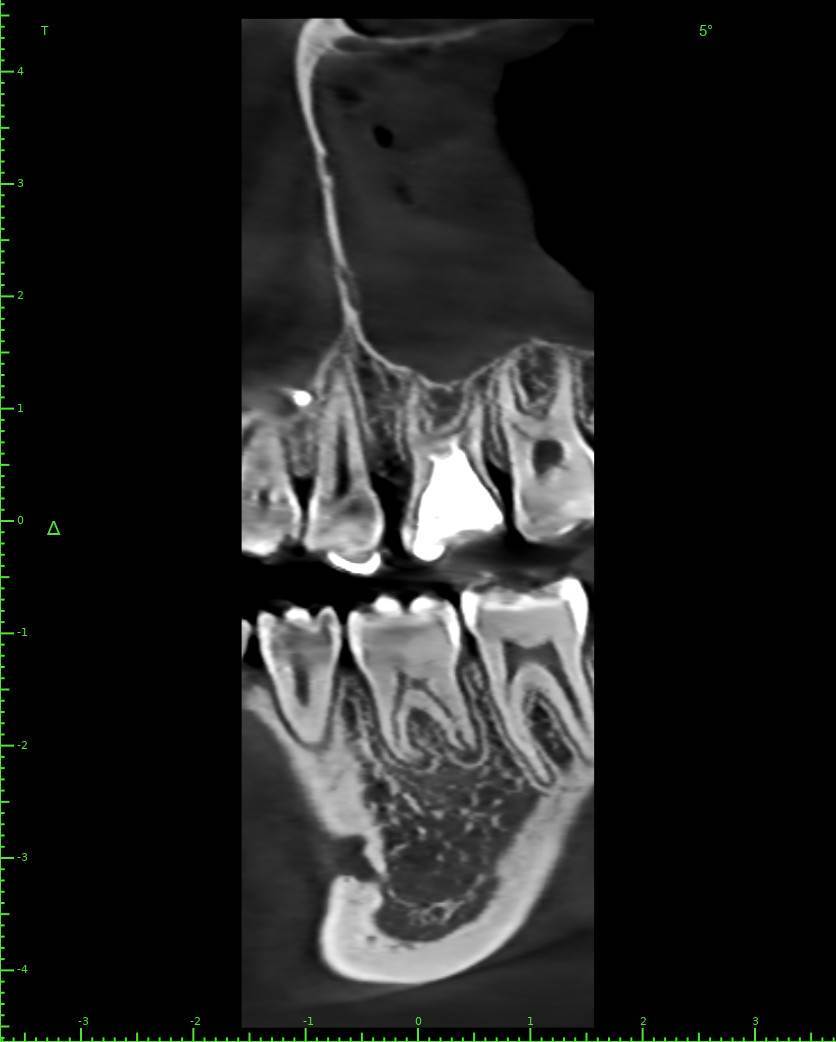

Женька Опубликовано 28 ноября, 2025 Поделиться Опубликовано 28 ноября, 2025 Всем привет, коллеги! 14 лет, терапевты ставят трещину по КТ (снимков до, к сожалению нет, косяк, каюсь). чуть сепарировав зуб и глянув на зуб под отлетевшим куском пломбы трещина "подтвердилась". Кейс на фото. Из интересного - маленький реколл в 1.5 года и спокойное перемещение зуба брекетами! 4 1 2 Ссылка на комментарий